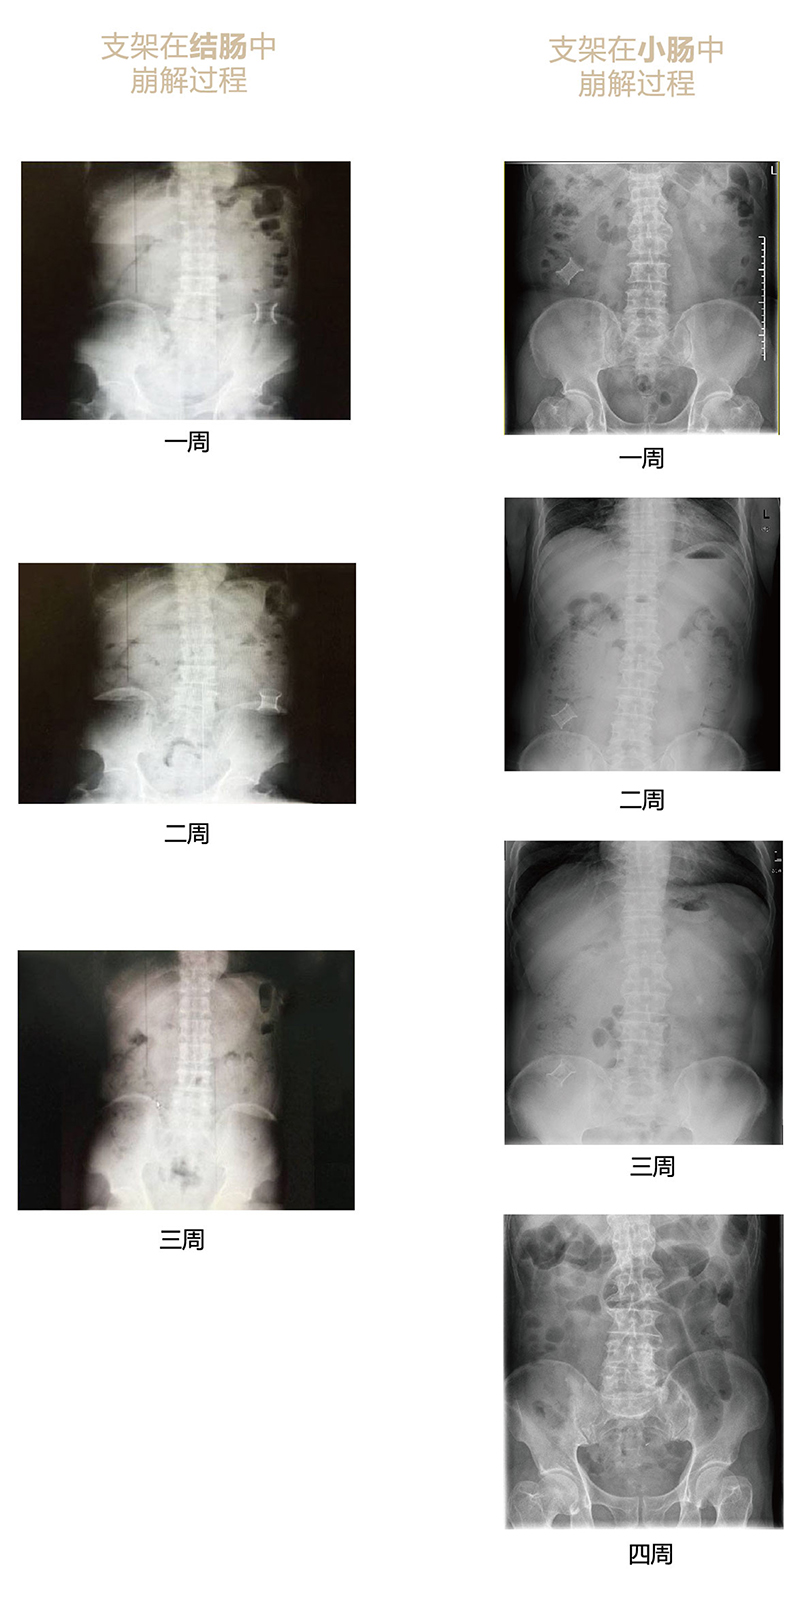

“可崩解腸道吻合器”由聚乙醇酸(PGA)與硫酸鋇按重量比7:1混合注塑制成,在X線下顯影,可動態(tài)追蹤可崩解腸道吻合器(支架)在腸道內(nèi)崩解過程。

為解決該問題,蔡秀軍教授在“支架法空腔臟器吻合技術(shù)”的理念基礎(chǔ)上,又發(fā)明了“蔡氏腸轉(zhuǎn)流術(shù)”,這是一種應(yīng)用“可崩解腸道吻合器HB型(可崩解腸轉(zhuǎn)流支架)”(發(fā)明專利號:201910794214.3),的支架法腸道轉(zhuǎn)流術(shù),此創(chuàng)新術(shù)式既能保護(hù)低位吻合口,更避免了回納術(shù)??杀澜饽c轉(zhuǎn)流支架在直腸癌根治術(shù)中植入遠(yuǎn)端回腸,可確保完全阻斷腸腔,用腸造瘺管在轉(zhuǎn)流支架近端行腸造瘺,起到完全轉(zhuǎn)流的作用。腸轉(zhuǎn)流支架在二至三周內(nèi)逐漸崩解,并在四周內(nèi)完全排出體外,恢復(fù)腸道通暢后拔除造瘺管,避免了傳統(tǒng)造口回納的二次手術(shù)。該創(chuàng)新術(shù)式具有方法簡單、吻合時(shí)間短、人體內(nèi)無異物永久殘留、不破壞吻合口粘膜下血管,并能預(yù)防吻合口漏、可避免人工肛門留置及二次手術(shù)、治療周期可縮短至二至四周、患者生理心理創(chuàng)傷顯著減少。